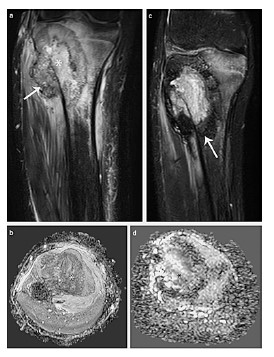

Osteosarcoma en joven de 13 años.

El tratamiento quirúrgico del osteosarcoma implica la escisión del tumor y la reconstrucción de la extremidad. La clasificación de Enneking establece los márgenes quirúrgicos en cuatro tipos: intralesionales, marginales, amplios y radicales. Debido a que los márgenes intralesionales y marginales se asocian con altas tasas de recurrencia local, se prefieren los márgenes amplios, que permiten el control de la enfermedad en hasta el 95% de los casos.

"La elección del margen quirúrgico depende de múltiples factores, como la ubicación anatómica del tumor, su patrón de crecimiento y la proximidad a estructuras críticas", explican los autores del estudio. En algunos casos donde hay compromiso neurovascular o cuando la cirugía conservadora limitaría la funcionalidad, la amputación sigue siendo la opción más viable. Además, la reconstrucción quirúrgica debe adaptarse a la edad del paciente y su potencial de crecimiento, lo que representa un desafío en niños en desarrollo.

Lesión femoral de osteosarcoma.